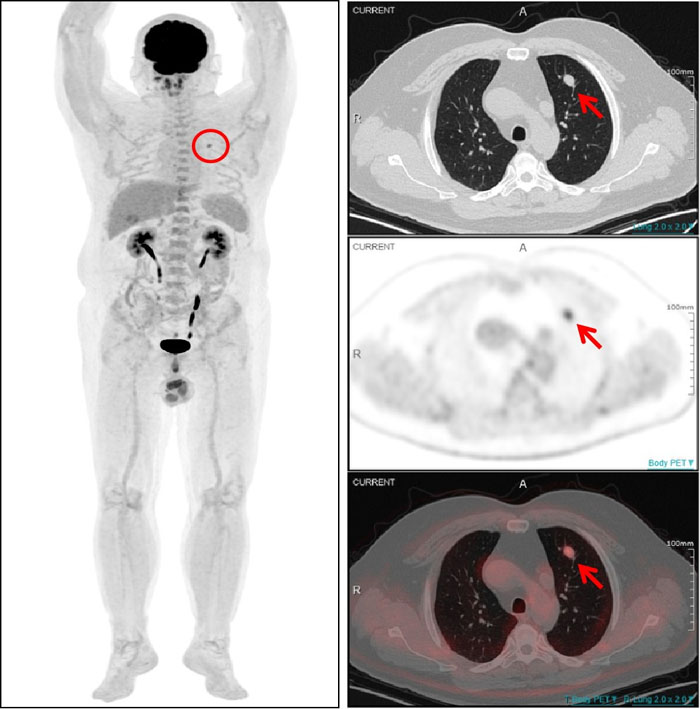

PET/CT显示:该结节伴明显异常葡萄糖高代谢(SUVmax4.5),为肺转移灶。

‌一名54岁男性患者曾在1年半前接受了左大腿脂肪肉瘤切除术,术后规律复查。一次常规CT检查发现其左肺上叶存在一个软组织结节,随后复查显示该结节有所增大,直径约为1.0cm。面对这一疑似转移的挑战,全景动态Total-body PET/CT 清晰显示左肺上叶结节伴明显异常葡萄糖高代谢,提示该结节为肺转移灶。基于检查结果,医生能够及时为患者制定更加个体化的治疗方案。对该患者的诊断,彰显了全景动态Total-body PET/CT 在癌症诊断领域的非凡实力。